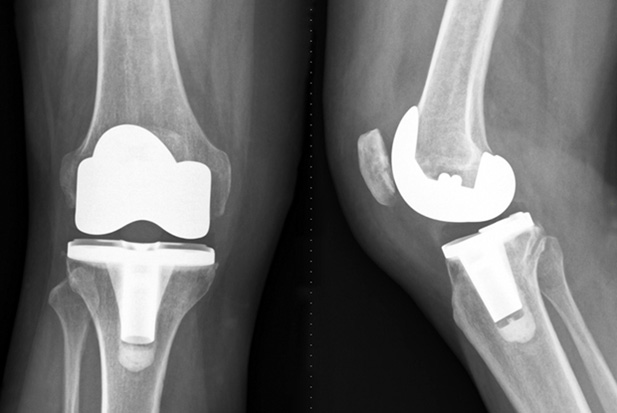

¹«¸­ ¼ö¼úÀº ¹Ý¿ù»ó¿¬°ñÆÄ¿­À̳ª ¿¬°ñÀÇ °æ¹ÌÇÑ ¼Õ»óÀÎ °æ¿ì °üÀý°æ ¼ö¼ú, °ñ°üÀý¿°ÀÌ ½ÉÇÑ °æ¿ì Àΰø°üÀý ġȯ¼úÀ» ¹Þ½À´Ï´Ù.